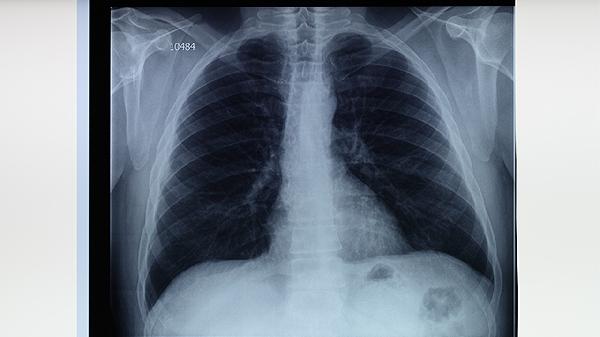

肺结核患者应保证每日摄入60-80克优质蛋白,优先选择鱼肉蛋奶等易消化食物,避免辛辣刺激饮食。居住环境需保持通风干燥,每日紫外线消毒30分钟,康复期可进行八段锦等温和运动增强肺功能。治疗期间严格遵医嘱完成6-9个月规范用药,定期复查胸部CT和痰培养,接触者应进行预防性筛查。